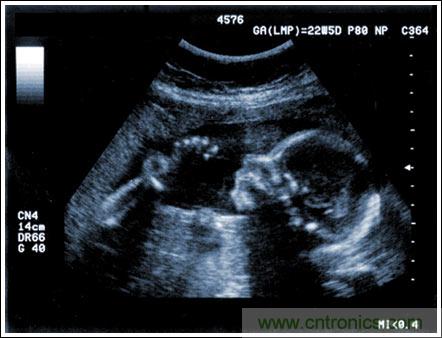

通過發(fā)射超聲能量進入人體,接收并處理返回的反射信號,相控陣超聲系統(tǒng)可以生成體內器官和結構的圖像,映射血液流動和組織運動,同時提供高準確度的血流速度信息。傳統(tǒng)設計中,構建這樣的成像系統(tǒng)需要大量的高性能相控陣發(fā)射器和接收器,使得車載設備體積龐大且價格昂貴。近年來,隨著集成工藝的進步,設計人員能夠獲得小尺寸、低成本而且高度便攜的成像系統(tǒng)方案,并可達到接近大型成像設備的性能指標。而新的設計挑戰(zhàn)依然存在,即在進一步提高方案集成度的同時提高系統(tǒng)性能和診斷能力。